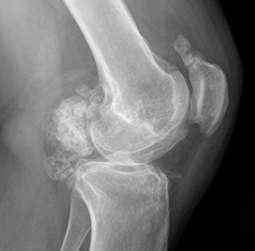

En la Rx simple hay cuerpos libres calcificados, prominencia de tejidos blandos, conservándose el espacio articular y la densidad ósea. Pueden encontrarse erosiones escleróticas del hueso adyacente. (19). (Fig 70).

Fig 70. Condromatosis sinovial.

A: Rx lateral. Imagen calcificada de contornos lobulados en la parte posterior de la articulación, que corresponde a condromatosis sinovial.